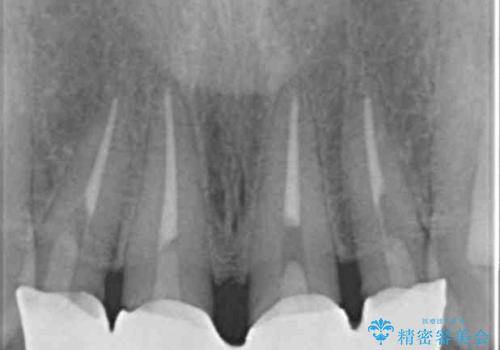

レントゲンを撮影したところ土台の植立も不十分であったため、土台からやりかえることにしました。